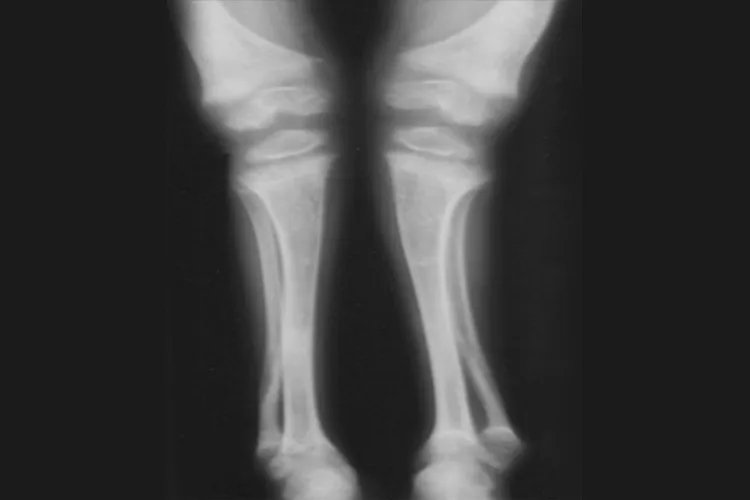

活动期活动期6月龄以内婴儿的佝偻病以颅骨改变为主,前囟边较软,颅骨薄。6月龄以后,颅骨软化消失,至7-8个月时,变成“方盒样”头型即方头。骨骺端因骨样组织堆积而膨大,出现佝偻病串珠,手腕足踝部亦可形成钝圆形环状隆起,称手足镯。1岁左右的小儿可见到胸骨和邻近的软骨向前突起,成“鸡胸样”畸形,严重佝偻病的小儿,膈肌附着处的肋骨受膈肌牵拉而内陷,胸廓的下缘可形成一水平凹陷,称作肋膈沟或郝氏沟。由于骨质软化与肌肉关节松弛,小儿开始站立与行走后双下肢负重,可出现股骨、胫骨、骨弯曲,形成严重膝内翻或膝外翻。